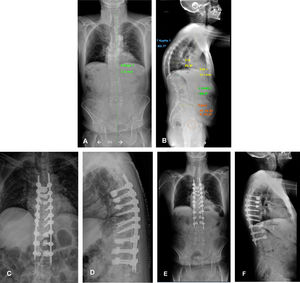

Fig. 3 shows the case of an insufficiency fracture, managed orthopaedically, which progresses to sagittal imbalance.

Fig. 4 shows a clinical case of MIS instrumentation of a patient with sagittal imbalance due to vertebral fractures. Note the cement augmentation of the screws to increase screw strength.

Male, 71 years old, who suffered a fall from standing height in January 2023. Since then, he has presented with dorsolumbar pain. Images A and B show a teleradiograph showing the significant sagittal imbalance caused by multiple vertebral fractures, resulting in hyperkyphosis. Images C and D show the first postoperative X-ray. Long posterior instrumentation was performed, with minimally invasive techniques and cement augmentation of the most cranial and caudal screws. Images E and F show the first postoperative teleradiograph, at one month, where the restoration of sagittal balance is evident.